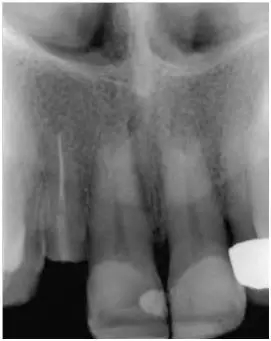

12至22牙的影像學(xué)檢查(圖5);

影像學(xué)檢查:根尖和根中三分一段內(nèi)的根管充填尚可(牙膠和根充糊劑),圓柱形根樁(鈦)位于根上三分之一段,在根中三分之一可見(jiàn)X線阻射性材料(粘結(jié)劑)。

根尖周無(wú)病理性變化

根長(zhǎng)度約15mm

圖5:外傷9天后的影像學(xué)檢查:12牙牙冠在釉牙骨質(zhì)界水平處折斷并且可以看到根管充填和一個(gè)折斷的鈦根樁。所有牙齒均顯示輕度的水平向骨吸收,根尖周未發(fā)現(xiàn)異常。11至22牙牙冠被修復(fù)過(guò)。